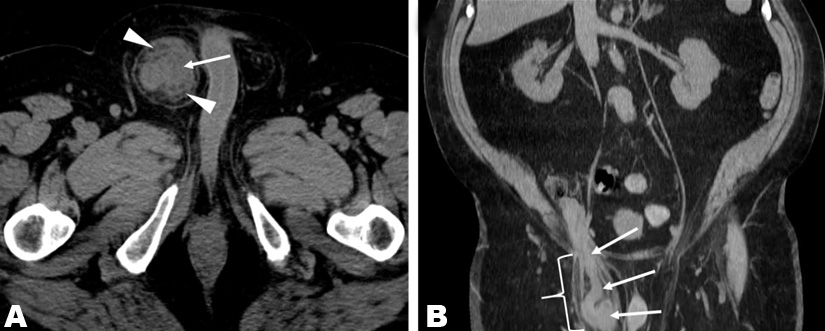

A 70-year-old man with a history of peripheral T-cell lymphoma in complete remission since 2012, presented with a three-week history of a tender ‘knot’ in his right inguinal/suprapubic region. He denied fevers, nausea, vomiting, and constipation. Physical examination was remarkable only for a 4x5 cm firm mass in the right suprapubic region. Complete blood counts and a comprehensive metabolic panel were normal except for a chronically elevated creatinine (1.9 mg/dL) and mildly elevated lactate dehydrogenase (279 units/L). Transaxial (Figure 1A) and coronal (Figure 1B) computed tomography (CT) images, obtained without intravenous contrast, revealed marked appendiceal thickening (arrows) and periappendiceal fat-stranding (arrowheads), suspicious for acute appendicitis. As shown in Figure 1B, the appendix was located within an indirect inguinal hernia sac (bracket), an entity known as an Amyand hernia. There was no evidence of appendiceal perforation. One day later, the patient underwent a laparoscopic appendectomy and open primary right inguinal hernia repair with a post-operative diagnosis of “acute, perforated appendicitis incarcerated within an indirect right inguinal hernia.” In addition to acute- on-chronic inflammation in the hernia sac, pathology revealed diffuse large B-cell lymphoma of the appendix. Subsequent staging by fluorodeoxyglucose (FDG)- PET/CT revealed multiple FDG-avid liver lesions consistent with stage IV lymphoma. The patient subsequently achieved a complete response with R-CHOP chemotherapy.

Figure 1: Computed tomography (CT) images obtained without intravenous contrast; (A) transaxial image, (B) coronal image.